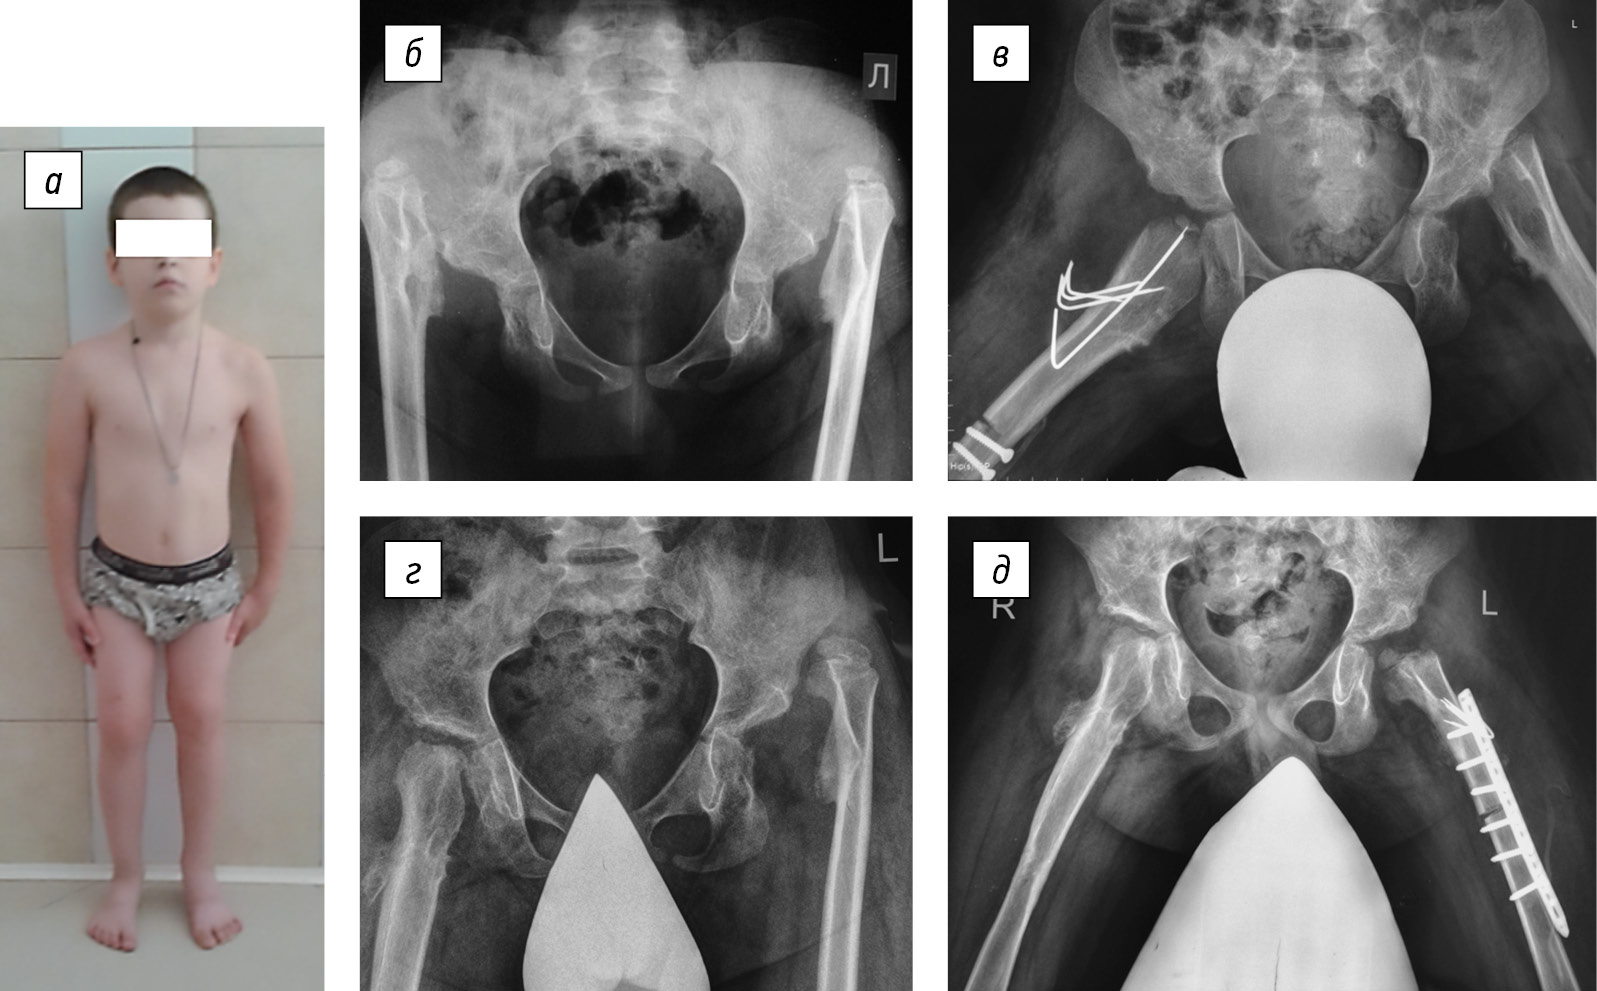

The child was admitted to the H.I. Turner National Medical Research Center for Сhildren’s Orthopedics and Trauma Surgery at the age of 6 years. He underwent surgical interventions to stabilize the hip joints, with an interval of 1.5 years. Therefore, in 2014 and 2015, hip arthroplasty was successively performed using demineralized bone and cartilage allografts. Concurrently, shortening detorsion osteotomies of the femoral bones were performed for joint decompression (Fig. 1).

Fig. 1. Appearance of the patient (a) and hip joint radiographs before (b) and at their surgical stabilization stages (c–e)

Regular rehabilitation measures in the postoperative period and the long term enabled stability maintenance and satisfactory hip joint function to date (Fig. 2).

Fig. 2. Appearance of the patient (a–c) and hip joint radiograph (d) after hip joint stabilization and left femur lengthening (2021)

Concurrently, other anatomical and functional disorders of the affected limb segments appeared in the growth process, namely, left femur shortening and left femur and tibia antecurvation deformity, which imitates knee joint flexion contracture, as well as left elbow joint varus deformity (2020) (Fig. 3).

Fig. 3. Left knee (a) and elbow (b) joint deformities at the treatment stage